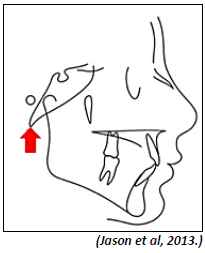

Analise a imagem a seguir.

Como se chama o ponto cefalométrico indicado pela seta?